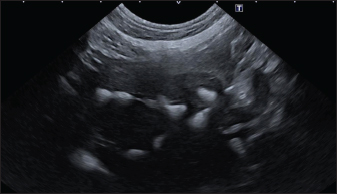

In the branched pattern, mineralizations were usually sub-centimetric or centimetric and they replicated the shape of the intrahepatic biliary tree (Fig. 3). Also in this case, sub-centimetric and centimetric IBTM determined a focal dilatation of the biliary ducts observed in 65.6% of dogs (21/32) (Fig. 4). In six of them (18.7%), we found millimetric IBTM randomly distributed in the liver.

Fig. 4. Ultrasound image of the liver showing centimetric IBTM, generating acoustic shadow, with an aligned pattern. In the image, we can observe a focal dilation of the larger biliary duct, upstream and downstream to the calculi, because of the presence of the choleliths themselves.